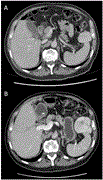

Hepatic angiomyolipoma, misdiagnosed as hepatocellular carcinoma

Bárbara M Marinho and others

Journal of Surgical Case Reports, Volume 2023, Issue 10, October 2023, rjad556, https://doi.org/10.1093/jscr/rjad556